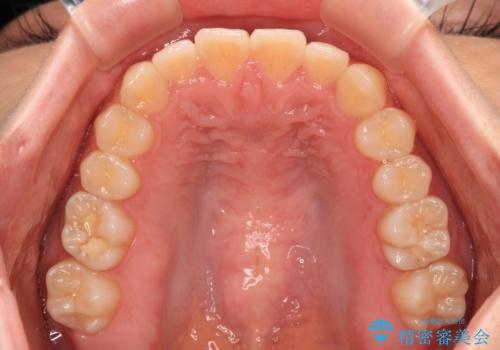

前歯のクロスバイト インビザラインによる矯正治療

- 前歯のクロスバイトとデコボコを気にして来院された患者様です。

骨格的に下顎前突傾向であるため、自己管理が煩わしくないようであれば、インビザラインによる矯正治療がお勧めとなります。

インビザラインを用い、下顎歯列を後方に移動させながら全市の被蓋を改善し、歯並びを整えていくこととしました。

途中マウスピースが使用できず、来院されない期間があり、治療期間は長くかかりましたが、無事に治療を終えることができました。